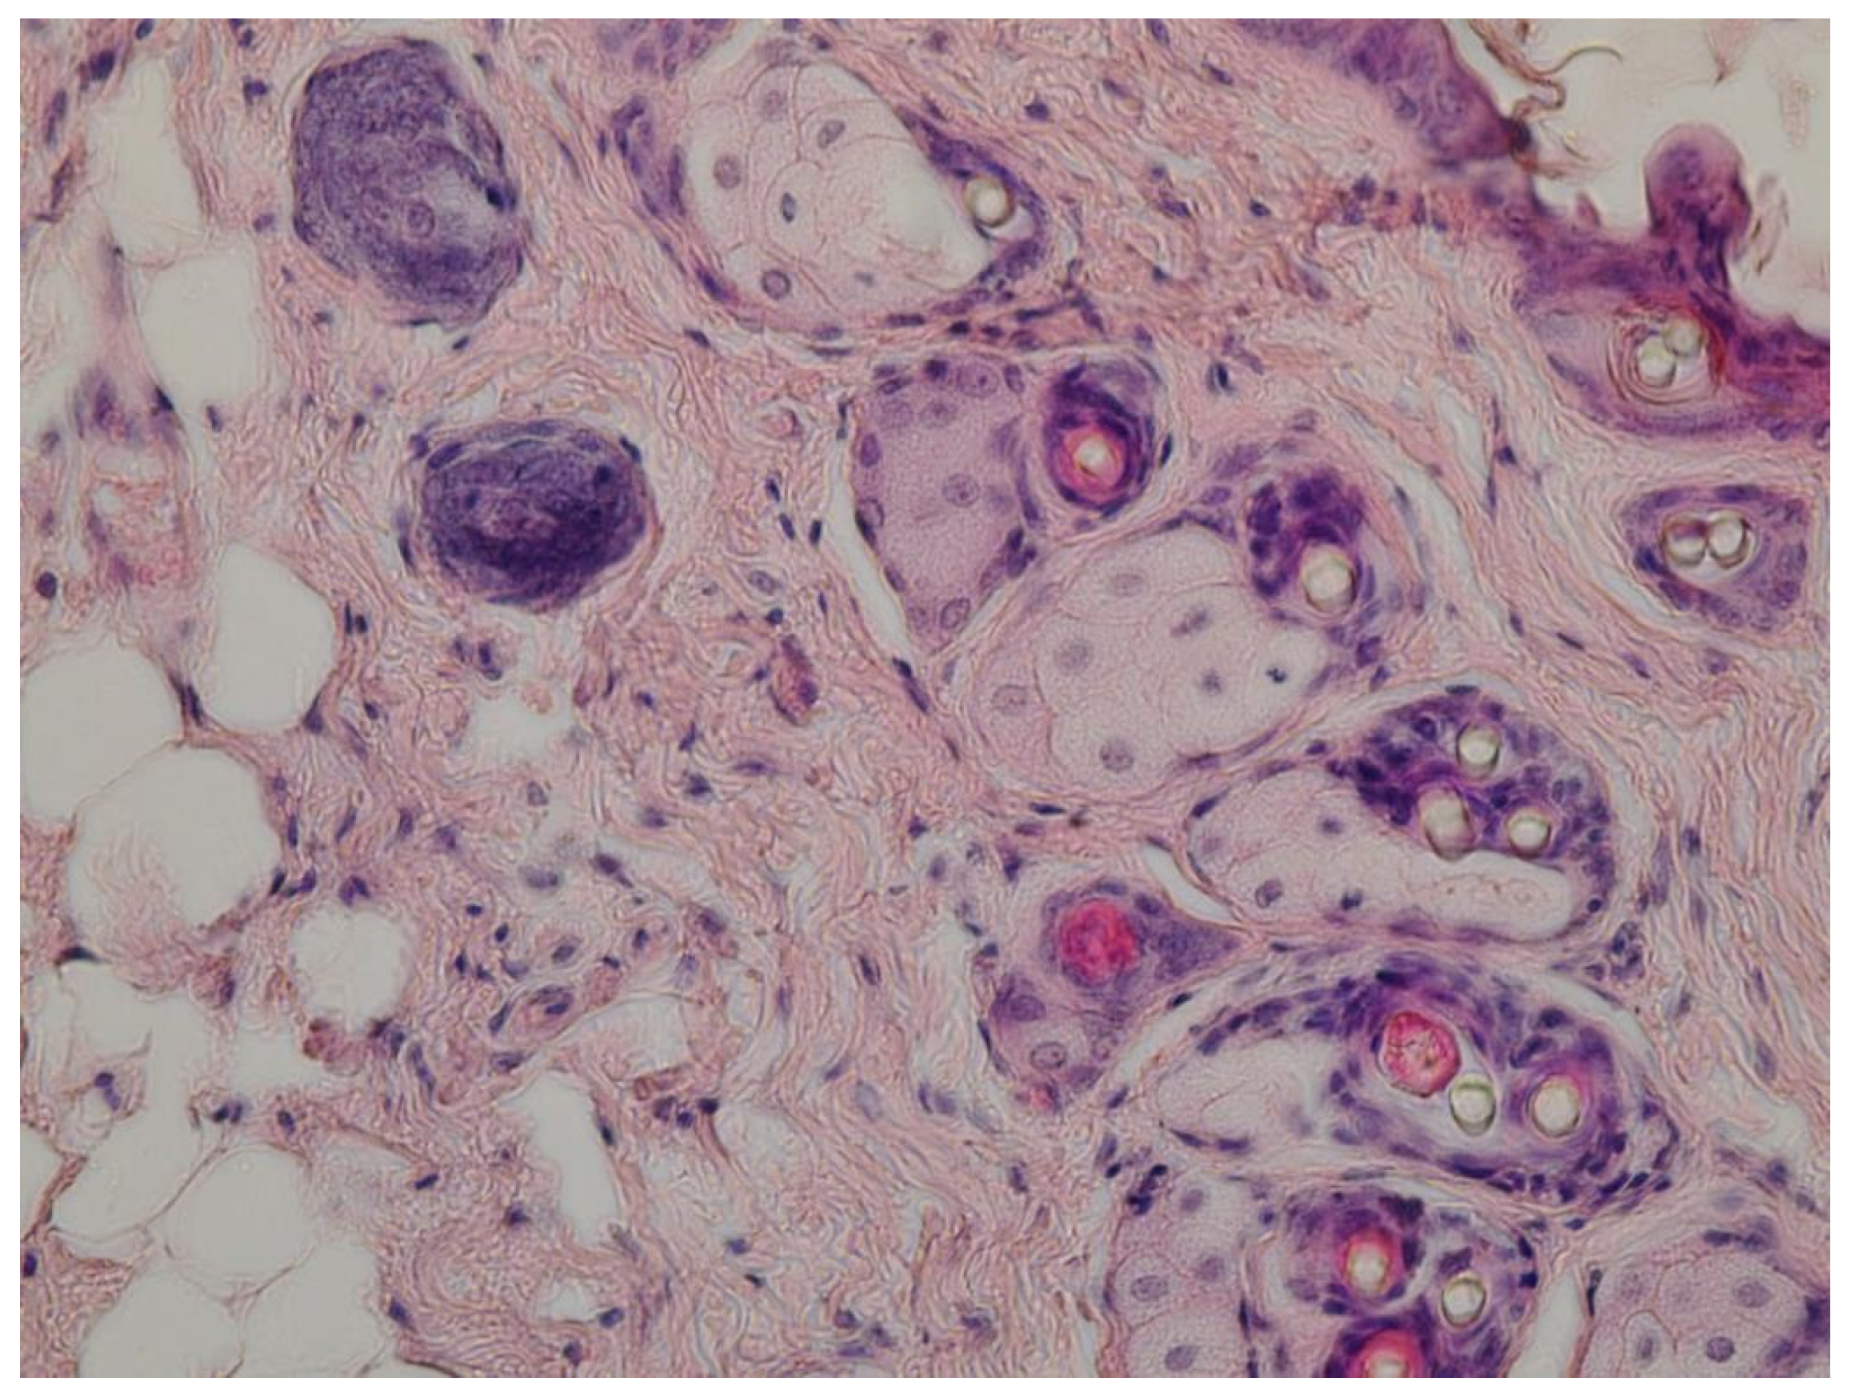

4.6. Investigation of Wound-Healing Ability of ZnO NPs Gels

4.7. Histological Research

- (1)

- A group treated with a gel of ZnO MPs and hydroxyethyl cellulose (control group);

- (2)

- A group treated with a gel of ZnO NPs modified with hydroxyethyl cellulose (experimental group).